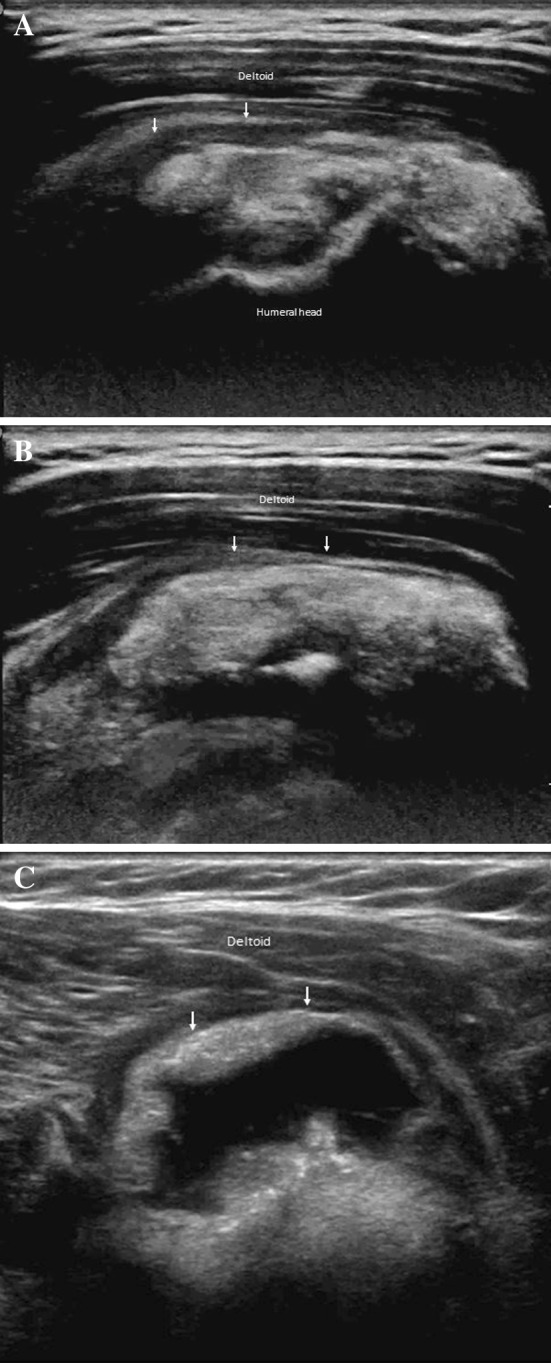

Fig. 1.

Calcium-related bursitis. From proximal to distal part (a, b, c) ultrasonography shows hyperechoic material (calcium) within the effusion in the subacromial–subdeltoid bursa. The bursa presents thickened walls

In cases of intrabursal penetration of the calcification, at US (Fig. 1) (movie 1) and magnetic resonance (MR) examinations (Fig. 3), the subacromial–subdeltoid bursa presents thickened walls and appears filled with dishomogeneous fluid containing calcium and debris. Bursal-side partial-thickness tendon tears may occur during extrusion of the calcifications into the subacromial bursa. Standard radiographs of the shoulder can detect multiple ill-defined calcifications between the deltoid and supraspinatus (Fig. 2).